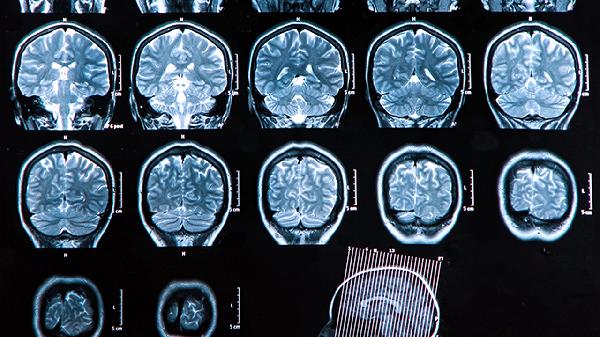

脑血栓的治疗方法

脑血栓的治疗方法主要有溶栓治疗、抗凝治疗、抗血小板聚集治疗、神经保护治疗和手术治疗。脑血栓通常由动脉粥样硬化、高血压、糖尿病、高脂血症、心房颤动等因素引起,表现为突发性偏瘫、言语障碍、意识模糊等症状。